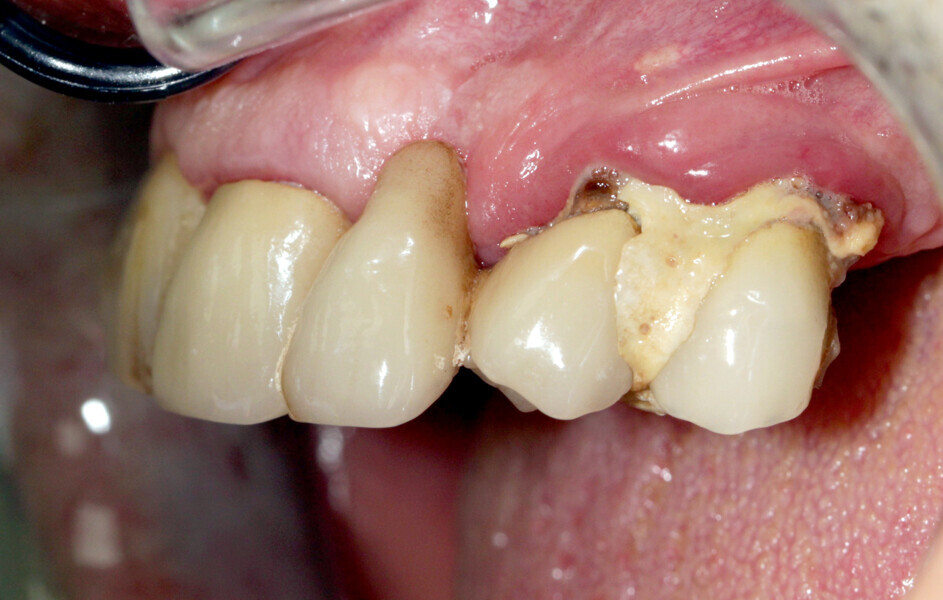

A 62-year-old patient with a bridge from tooth #21 to tooth #27 requiring replacement, teeth #21, 23, 24 and 27 with abutments and the crown of #22, 25 and 26 missing, was treated. The ridge of tooth #22 exhibited a transverse bone insufficiency which would have allowed the placement of an implant, but the aesthetic outcome would have been unsatisfactory (Fig. 10). First, the bridge of tooth #24 was sectioned distally and the root of tooth #27 extracted. After a two-month healing period, the patient was treated with simultaneous extraction, implantation and aesthetic restoration. The bridge was sectioned distally at tooth #21, a full thickness flap was elevated and the teeth #23 and 24 were extracted, allowing the bone defect at tooth #22 to be assessed (Fig. 11). Implants were placed into sites #22, 24 and 27. The root of tooth #23 allowed us to compensate for the bone defect and achieve a satisfactory aesthetic result. The root was prepared as described. The radicular graft was fixated away from the ridge, the edges of the graft in contact with the alveolar bone (Fig. 12). The spaces between the ridge, the graft and the alveoli were filled with a synthetic, hydroxyapatite-based biomaterial, the flap was stretched and sutured around the healing abutments, an impression was taken, and a temporary prosthesis from implant #22 to 27 was made during the day by the laboratory and fitted the same evening. The stitches were removed on the tenth day and the bridge after two months to check for the successful osseointegration of the implants. The osteosynthesis screws were not removed in this case because they were not visible under the gingiva (Figs. 13 & 14). A CBCT assessment was performed after six months to check that the graft had taken successfully. Finally, our colleague fitted the definitive prosthesis.